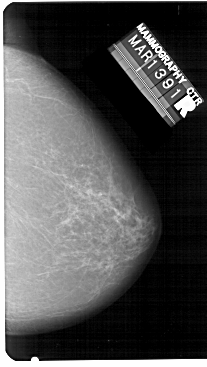

A_1341_1.RIGHT_MLO

RIGHT_CC LINES 5491 PIXELS_PER_LINE 3091 BITS_PER_PIXEL 12 RESOLUTION 43.5 NON_OVERLAY

RIGHT_MLO LINES 5491 PIXELS_PER_LINE 3496 BITS_PER_PIXEL 12 RESOLUTION 43.5 NON_OVERLAY